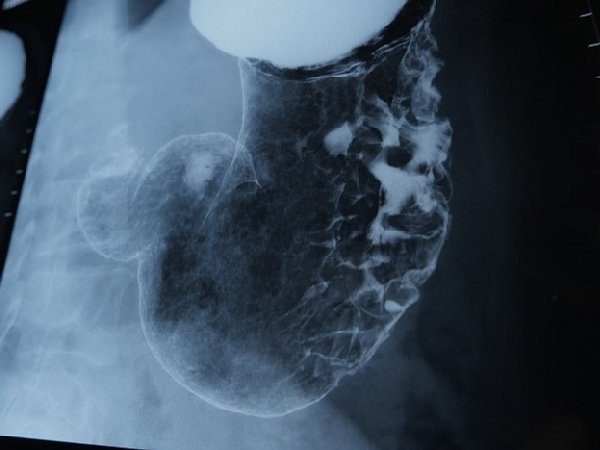

スキルス性胃がんに侵された胃